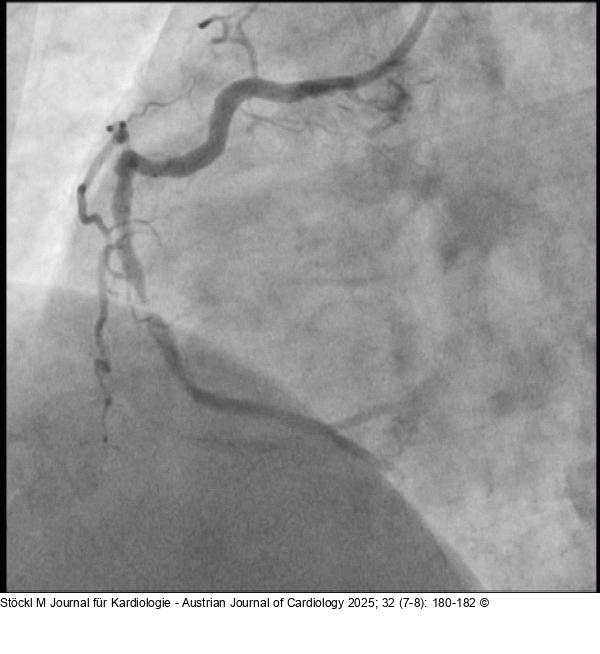

Abbildung 1: RCA

RCA: proximal wirksam und im mittleren Hauptstamm hochgradig stenosiert (schuldige Läsion) |